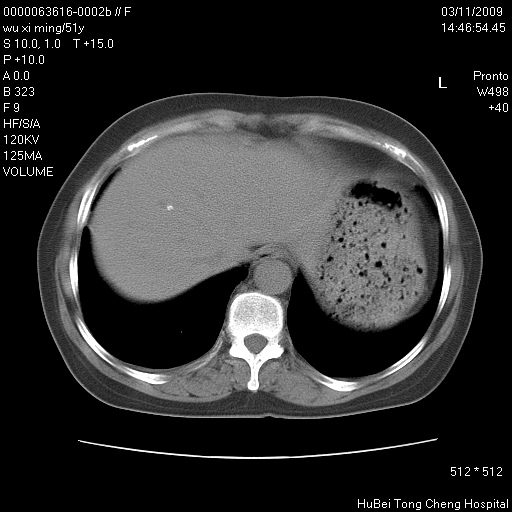

患者 女,51岁。因“胆囊炎,胆囊结石”,行常规术前胸部x线检查发现:右上肺结节病灶,建议行进一步检查。患者无咳嗽、咳痰及咯血等呼吸道症状,近期出现背部疼痛不适。

胸部ct轴位平扫(层厚10mm,螺距1.5,重建间隔10mm;部分层面:层厚3mm,螺距1.0,重建间隔3mm),图像如下:

右肺周围型肺癌伴肺内转移信胸椎转移

右肺周围型肺癌伴肺内转移及胸椎转移。已无手术机会。